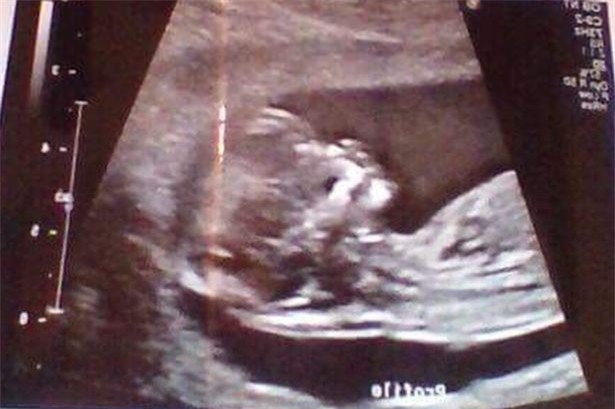

"Tôi thực sự cảm thấy khó chịu và phiền khi mọi người đưa ra những bình luận như vậy. Sau khi tôi cho họ xem phim siêu âm, ai cũng kinh ngạc. Trên thực tế, cả tôi và đứa trẻ trong bụng đều khỏe mạnh".

Hình chụp siêu âm con của Reanna hoàn toàn khỏe mạnh và phát triển bình thường.